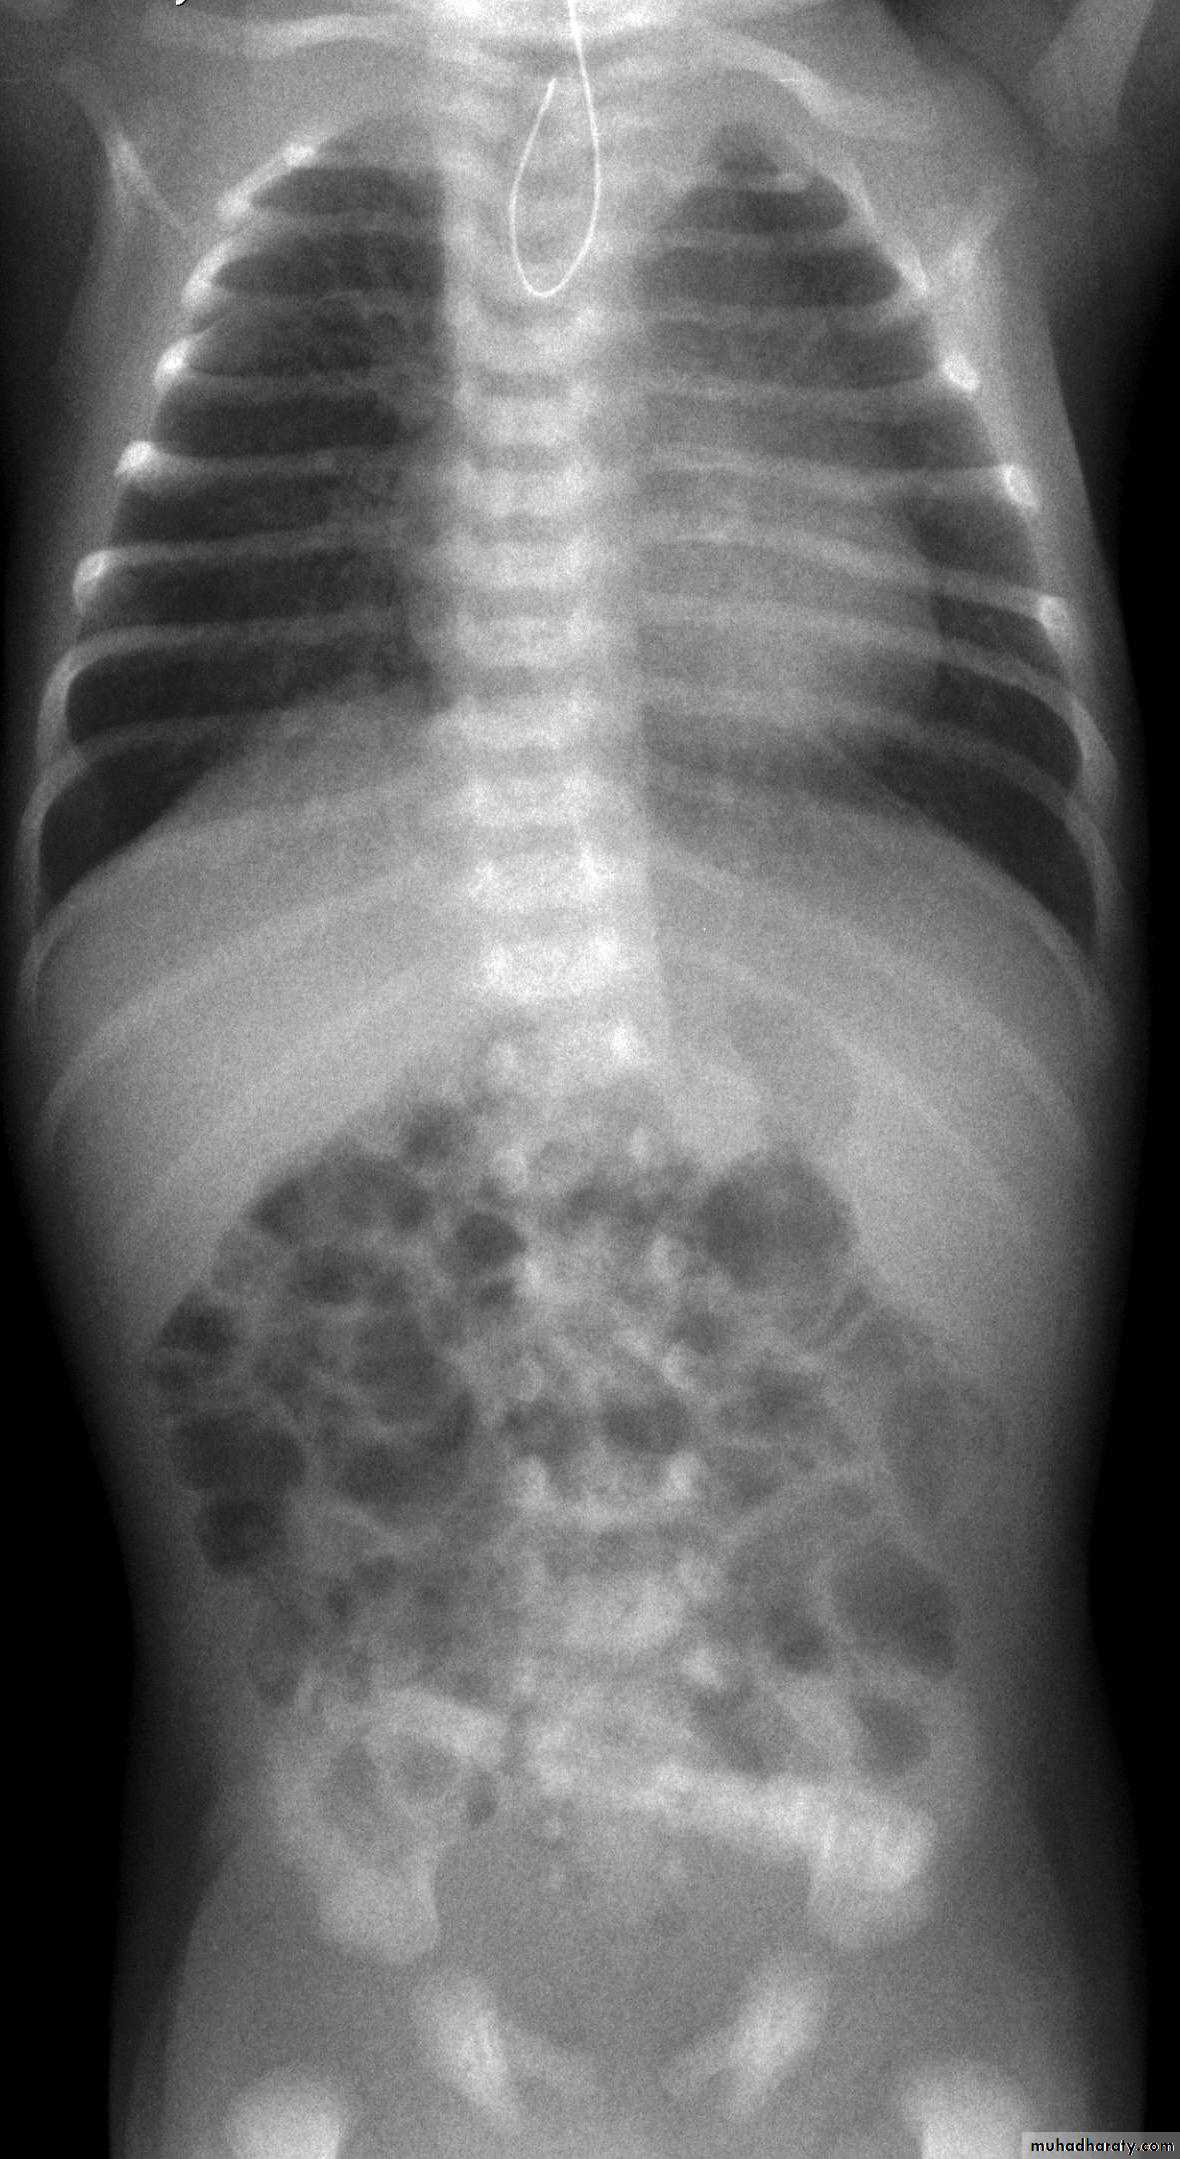

Spherical or oval bubbles of gas are seen in wall of LB in adults in pneumatosis coli

Linear streaks of intramural gas usually indicate infarction of the bowel wall

Gas in the wall of bowel in neonates, whatever its shape, is diagnostic of necrotizing enterocolitis